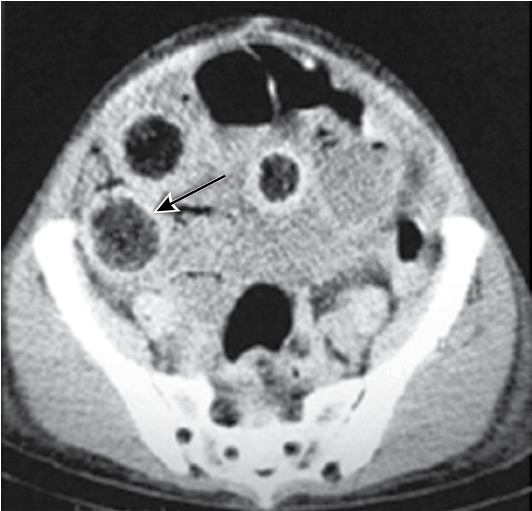

Paciente do sexo feminino, 18 anos, procura o serviço de Pronto-Socorro com relato de constipação intestinal há 15 dias, sem comorbidades conhecidas até o momento. Após lavagem intestinal com clister glicerinado, foi avaliada com melhora e alta no mesmo dia. Após 24 horas, evoluiu com vômitos fecaloides, distensão abdominal e febre não aferida. Observada alopécia traumática em região occipital. Após estabilização hemodinâmica, foi realizada tomografia computadorizada de abdome, evidenciando sinais representados em imagem abaixo.

Quais os diagnósticos sindrômico e etiológico mais prováveis?